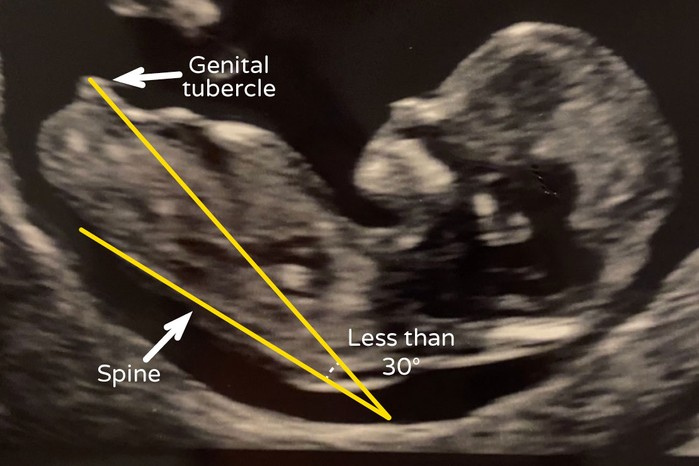

Nub theorie: het geslacht voorspellen bij de 12-weken echo

Wat is de nub theorie en hoe betrouwbaar is het? Alles over het voorspellen van het geslacht bij 11, 12 en 13 weken.